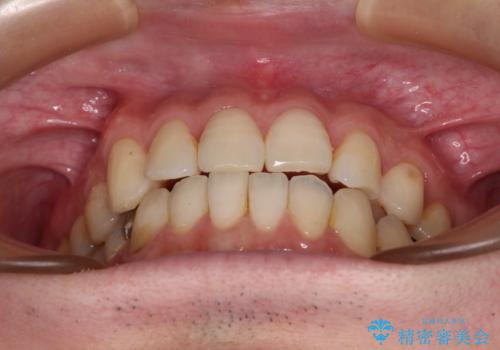

欠損のある歯列 インビザラインで整った歯並びに

- デコボコした前歯をセラミックできれいに揃えたいとのことで来院された患者様です。

歯を削って整えることは簡単ですが、健全な歯を削って後悔してからでは遅いため、矯正治療を提案しました。

はじめは矯正治療の期間が長いことに悩んでいらっしゃいましたが、ある程度整えば満足するだろうとのことで、インビザラインにて矯正治療を行うこととしました。

左上の犬歯が欠損しているため、正中の位置や奥歯の咬み合わせが理想的にならない点を了承していただきました。